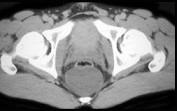

问题 男,21岁,下腹部一囊性肿块,无压痛,请结合图像,选择最可能诊断 ( )

选项 A.盆腔脓肿 B.结肠重复畸形囊肿 C.神经纤维瘤 D.神经鞘瘤 E.间质瘤

答案 B